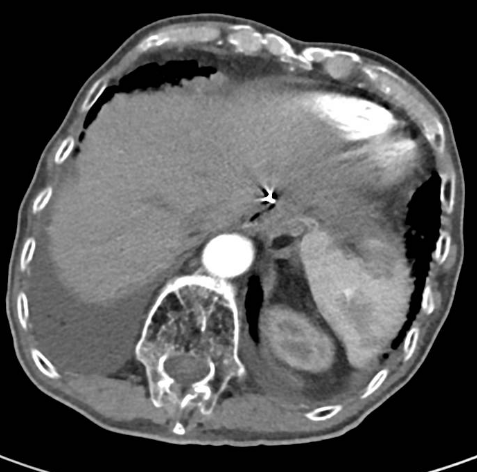

2020-01-08复查腹部CT:与患者前片(2019-7-8)比较显示:食管胃吻合口区低密度病变范围较前缩小。所示腹部其余病变较前未见明显变化,双肺片状高密度影,双侧胸腔积液。

△2020.01腹部CT

2020-08-31复查腹部CT:与患者前片(2020-1-8)比较显示:所示腹部病变较前未见明显变化。双肺高密度影范围较前缩小。

△ 腹部CT 2020.08